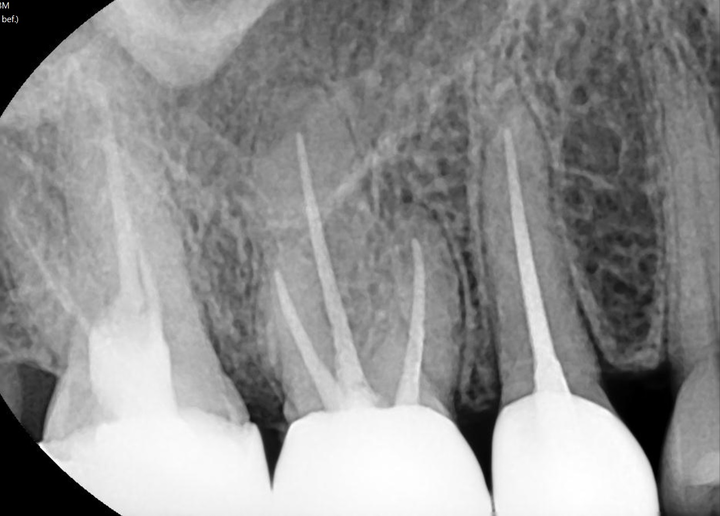

초진 시 치근단 방사선 영상에서 #16 치아의 근심협측 치근이 파절 후 치유된 상이 관찰되며(영상 1), 피신청인이 #17 치아의 수복물 재합착, #15, 16 치아의 근관치료를 계획한 것은 통상적인 치료계획으로 보임. 다만 #16 치아의 구강사진을 참조할 때 인레이 하방에 2차 치아우식이 의심되는 변색이 관찰되나 치근단 방사선 영상에서는 방사선 투과상이 관찰되지는 않고, #16 치아의 냉온검사, 치주낭 검사, 치수생활력 검사 등의 진료기록이 확인되지 않아 당시 치수 및 치아 상태를 알 수 없어 근관치료가 필요하였다는 진단에 대한 근거를 확인할 수 없음.

그 후 근관치료 및 크라운 수복치료는 통상적인 절차에 따라 진행된 것으로 보임(영상 2). 이후 저작 시 통증을 주소로 내원하였으나 해당 치아의 치근단 방사선 영상에서 근심협측 치근이 파절된 상(영상 3)이 판독되어 경과관찰이 필요하였을 것으로 사료됨.

초진 치근단 방사선 영상에서 #16 치아의 구개측 치근과 근심협측 치근이 파절되었다가 치유된 소견이 관찰되나 임상 증상이 없었으므로 진단이 어려웠을 것으로 보임. ○○대학교병원 치과보존과 진료기록에서 #16 치아의 구개원심측 치주낭이 깊어서 치조골 소실과 치근의 수직 파절을 의심해 볼 수 있으므로 치근 파절은 근관치료 이전에 이미 존재하였을 가능성이 있지만 언제 발생하였는지 그 시기를 특정하기는 어려움.

#16 치아 농양 발생 시 ○○대학교병원의 치근단 방사선 영상(영상 4)에서 #16 치아 근심협측 치근 치경부 1/3 부위에 방사선 투과상이 관찰되어 치근 파절로 인한 염증 소견으로 볼 수 있으며, 동시에 근심협측 치근과 구개측 치근의 치근단에도 방사선 투과상이 관찰되어 근관-치주 복합병소가 발생되었던 것으로 보이며, 이러한 상태에서 보존적인 치료의 예후가 불량하여 발치의 적응증이었다고 판단됨.